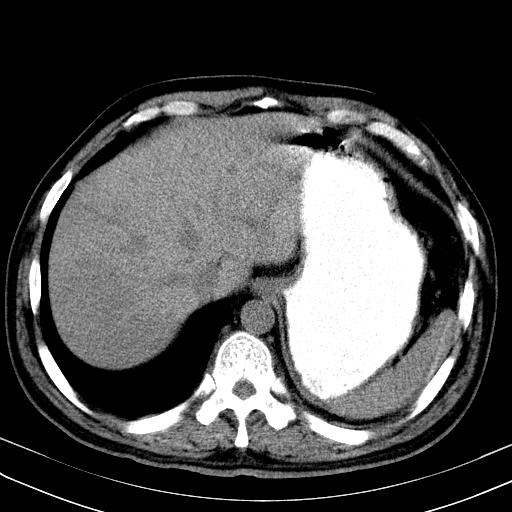

先行ct平扫,纵膈内多发软组织影,ct值约为36hu,以下为增强扫描和腹部平扫。

大家看看肝脏右叶片状低密度影是什么改变啊?

淋巴瘤?肝脏请增强后说啊

多发肿大淋巴结影,肝内改变需结合强化观察

多发肿大淋巴结影,肝内改变需结合强化观察。